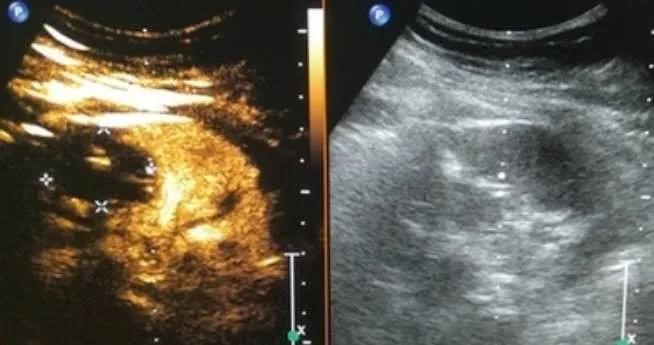

微波消融就是将一根特制微波针,经皮穿刺到肿瘤中心区域,在微波针的某一点上含有一个1毫米大小的“微型微波炉”,由它释放的微波磁场可以使周围的分子高速旋转运动并摩擦升温,从而使组织凝固、脱水坏死,达到治疗的目的。

相较传统手术、射频消融、氩氦刀治疗优势:有不受电流传导影响、受碳化及血流灌注影响小、温度上升快、消融范围大等特点;尤其适用于血流丰富肝脏、肾脏、肺脏肿瘤、和皮肤、浅表器官肿瘤(甲状腺、乳腺等);较传统手术创伤小、副反应少、恢复期短、体表无疤痕等优势。